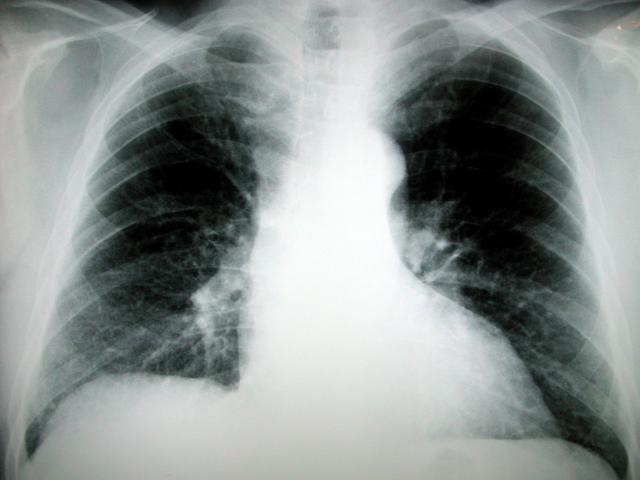

(NaturalNews) -- Why do some people get lung cancer -- even if they never smoke? New research suggests eating a lot of processed foods containing inorganic phosphates could be the explanation. What's more, the study also suggests that dietary changes to avoid these chemical additives may play an important role in lung cancer treatment.

According to the Centers for Disease Control (CDC), lung cancer is the number one cause of cancer deaths worldwide. The American Thoracic Society points out that over 75 percent of lung cancers are small cell lung cancers (NSCLC) and have an average overall 35-year survival rate of only 14 percent. Previous research has shown that about 90 percent of NSCLC appear to be activated by specific signaling pathways in lung tissue. The new study by Dr. Cho and his research team found that high amounts of dietary inorganic phosphates actually stimulate those same cancer-triggering pathways.